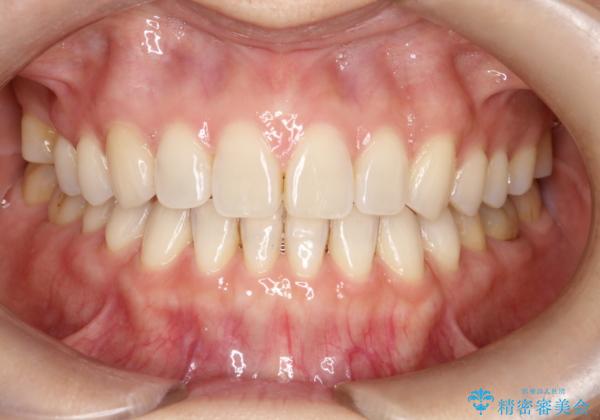

- 過去に矯正を行ったあと、前歯の後戻りを主訴に来院されました。

マウスピース矯正にて隙間を閉じる計画をたて、治療を行いました。